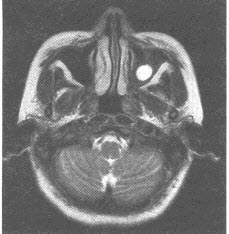

患者,男性,32岁,MRI检查发现左上颌窦腔内异常信号灶,图像如下,最可能的诊断为()

A:黏液囊肿

B:鼻窦炎

C:上颌窦癌

D:鼻真菌病

E:黏膜下囊肿